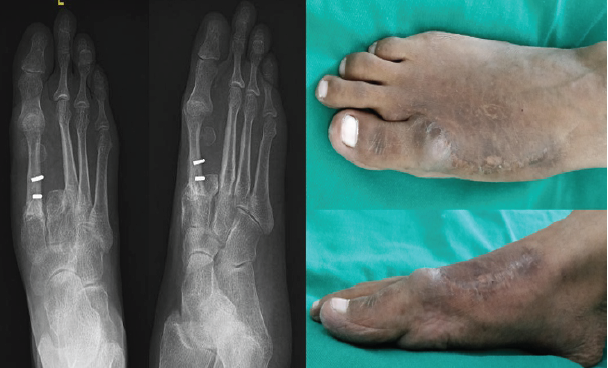

Figure 6: 4-year follow-up X-ray after removal of the plate and clinical picture.

K-wires were removed after 10 weeks, and she was made to weight bear gradually with the help of two elbow crutches. She started full-weight bearing walking at the end of 4 months. The patient was followed up every 6 months. She underwent removal of the plate after 4 years of the index surgery. Till her last follow-up (12 years), there is no evidence of any recurrence, and she is performing all daily routine activities without any difficulty.